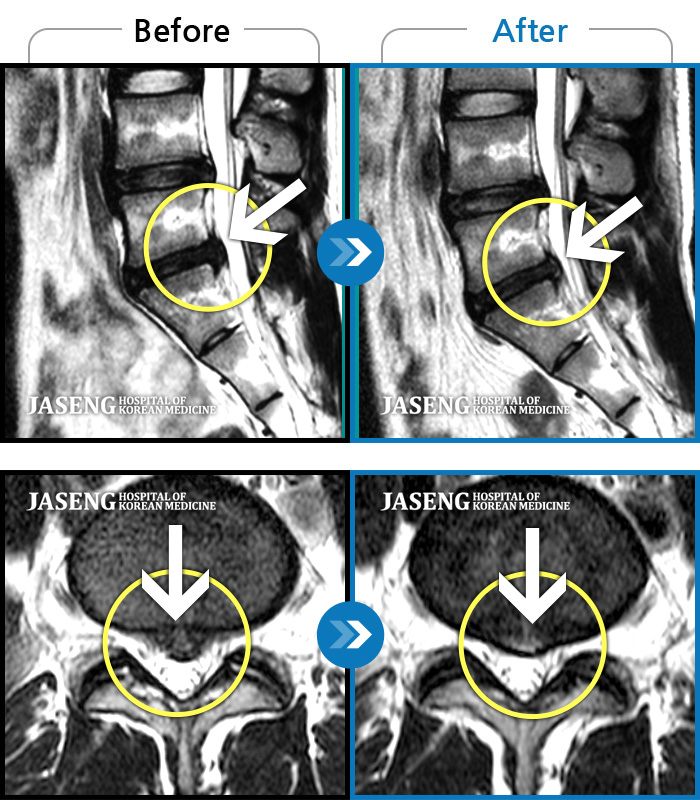

처음 내원 시 허리와 좌측 골반이 많이 아프고, 좌측 다리로 저림과 감각 저하가 있어서 보행이 원활하지 못했으며, 야간통으로 잠도 못 자고 통증 심하여 정상적인 활동이 힘든 상태셨습니다.

2023.09.16 ~ 2024.09.24